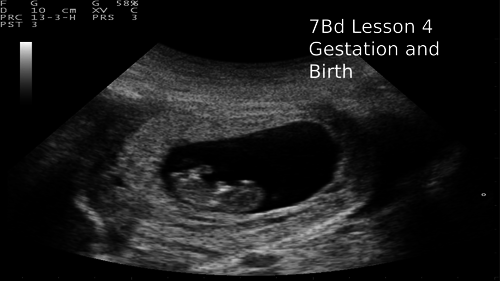

KS3 7B Reproduction Exploring Science

A complete set of PowerPoints and worksheets for the unit 7B reproduction.